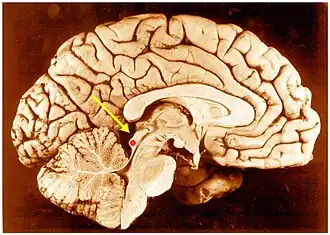

Inferior colliculus (red dot) in human brain, sagittal section.

The inferior colliculi together with the superior colliculi form the eminences of the corpora quadrigemina, and also part of the midbrain tectum. The inferior colliculus lies caudal to its counterpart - the superior colliculus - above the trochlear nerve, and at the base of the projection of the medial geniculate nucleus and the lateral geniculate nucleus.